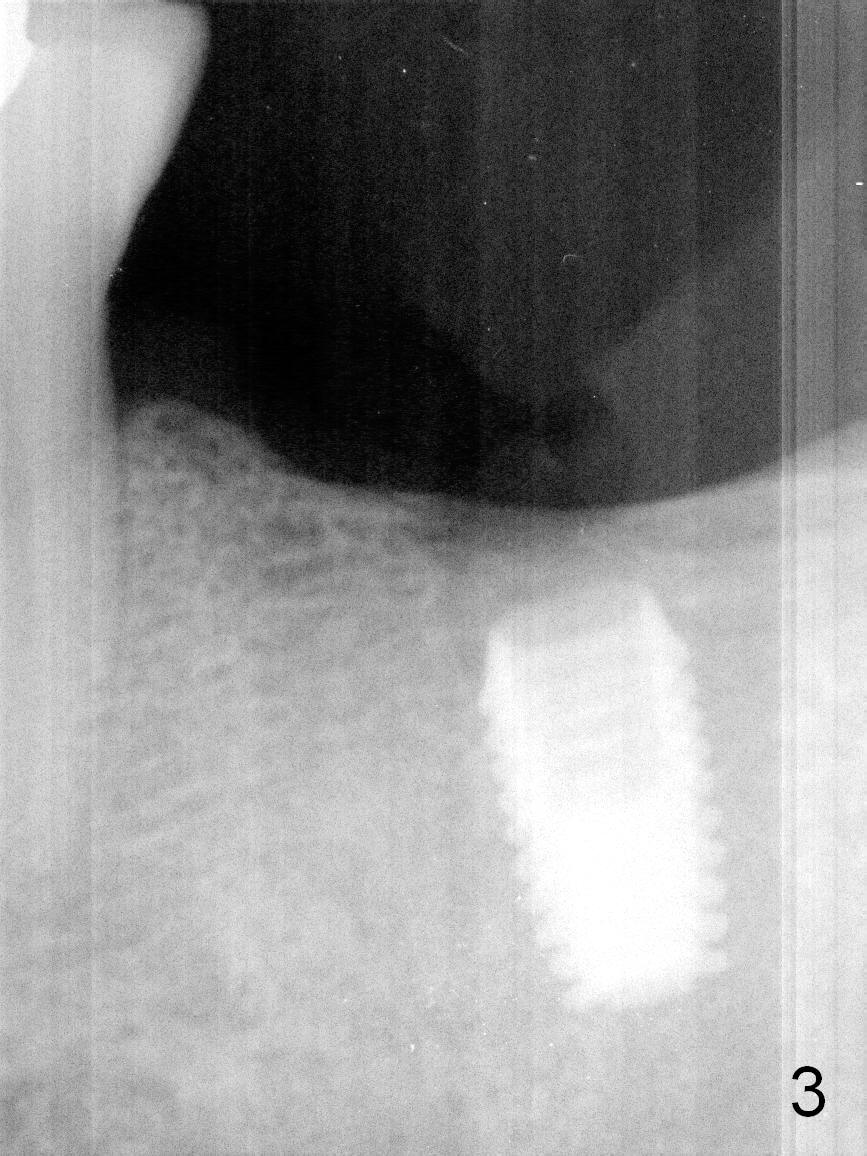

A 4.5x8 mm Bicon implant is placed (Fig.1-3) with intent to intrude the supraerupted opposing tooth once a provisional is fabricated. Now it is 5 months postop. In spite of poor implant position, the abutment or the crown has not become loose with increased bone density around the implant 2 years 3 months post cementation (Fig.4: *). Guide could easily overcome the deficiency.